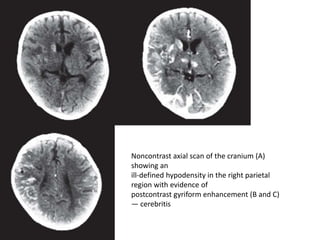

Noncontrast axial scan of the cranium (A)

showing an

ill-defined hypodensity in the right parietal

region with evidence of

postcontrast gyriform enhancement (B and C)

— cerebritis